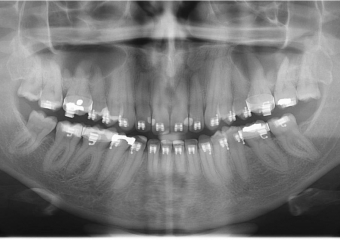

Raio x inicial

Raio x após a cirurgia